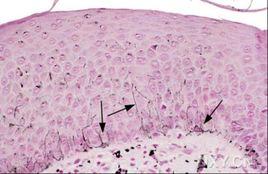

診斷方法是以臨床、X線和病理檢查結果為主依據,即經普通病理檢查發現病灶內有組織細胞浸潤即可確診。此症確診的關鍵在於病理檢查發現郎格罕細胞的組織浸潤。因此應儘可能作活組織檢查。

(10)免疫組織化學染色如前所述,近年發現郎格罕細胞具有CD1a的免疫表型,以抗CD1a單抗作免疫組化染色呈特異性陽性反應。此外對以下四種酶也可呈陽性反應,即S-100神經蛋白、α-D-甘露糖酶、ATP酶和花生凝集素。